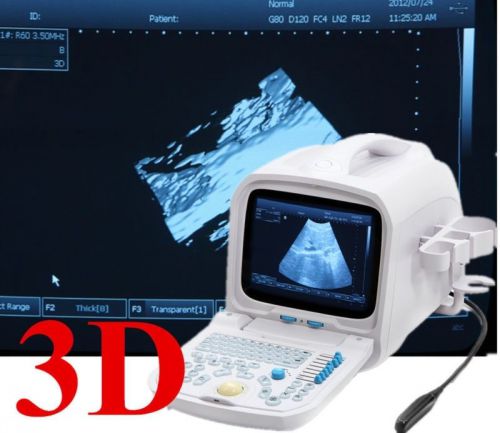

| Model | RUS-9000F |

3D Working Station Digital Portable Ultrasound Scanner machine CONVEX Probe 2015